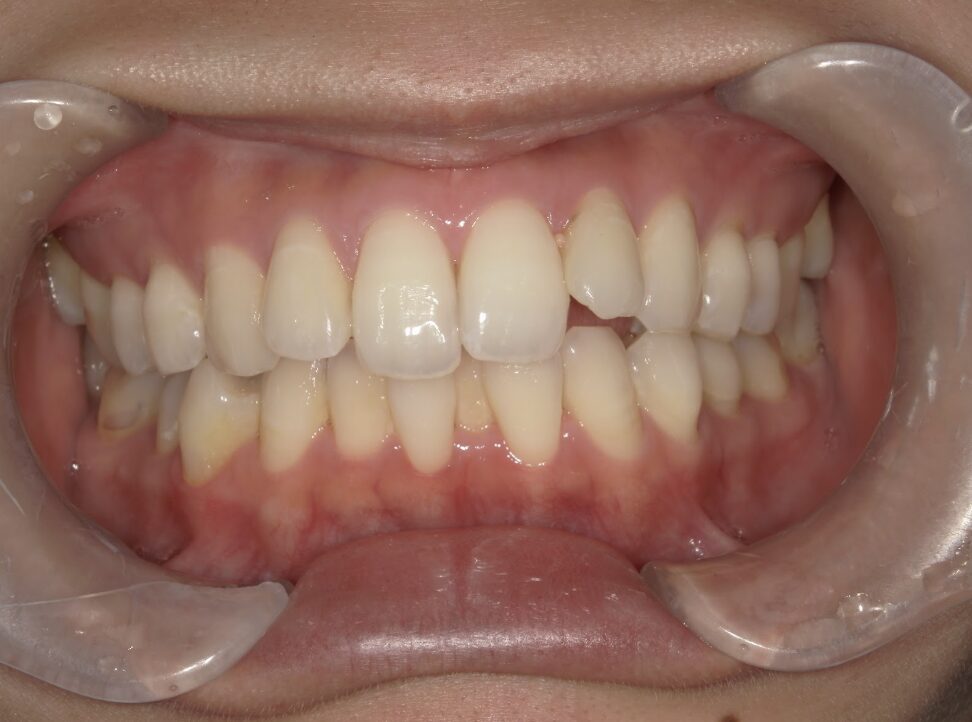

前歯が全く当たっていないを主訴に当院を受診され、開咬・上顎前突・下顎叢生を認めました。

上顎左右4番抜歯を行いIPRを使用してマウスピース型矯正装置(インビザライン)を使用し、改善を行いました。

年齢/性別20代女性

抜歯部位上顎左右4番

治療期間1年9ヶ月